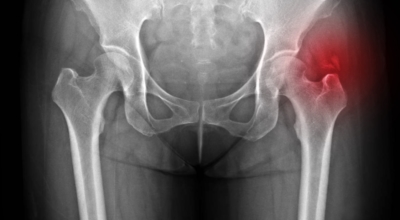

고관절염은 고관절에 나타나는 관절염을 말하며 고관절의 연골이 닳게 되면서 뼈와 뼈가 서로 부딪히며 통증을 일으키게 돼요. 고관절염 초기 증상으로는 사타구니 부위가 불편하게 느껴지며, 무리하면 통증이 발생할 수 있으며, 관절염 증상이 심해지면서 사타구니에서 느끼던 통증이 허벅지와 엉덩이 통증으로 이어지기도 하는데, 고관절염 통증 증상으로 초기에는 허리 통증이 나타나 허리 질환과 혼동하기 쉬우며 각별히 척추질환이 있는 사람은 고관절 통증과 마찬가지로 엉덩이, 다리 통증이 동반되기 때문에 훨씬 헷갈리는 경우가 많습니다.

이 증상은 퇴행성 고관절염에 의해 생기는 현상으로 보통은 중장년층에게 자주 일어나는 질병입니다. 이 질병은 관절과 관절 사이에 존재하는 연골이 닳아 없어지면 관절 내부와 주위에 염증과 통증을 동반합니다. 보통 골반 아래단에 뻐근한 증상을 일으키고 양반다리 자세를 할 때 통증이 심해져요.

더불어 계단을 오를 때 통증이 심해지고 오래 걷는것도 힘들어 져요. 원인은 노화로 인한 연골 마모, 과체중, 고관절 질환을 방치하는 경우 입니다. 치료방법은 적절한 운동과 소염제를 사용하기도 하며 심할경우 수술 치료가 시행 될 수 있어요.

각별히 젊은 남성에게 잘 발생하며 엉덩이와 골반 주위에 뻐근한 통증이 동반되며 정상적인 보행이 되지 않고 절뚝거리는 증상이 나타난다면 대퇴골두 무혈성 괴사일 가능성이 있답니다. 이 증상은 괴사 부위의 골절이 발생되어 고관절 손상으로 이어지면 발생하는 증상으로 아직까지 정확한 원인은 규명하기 힘드나 과음이나 고지혈증, 스테로이드 과남용이 영향을 줄 수 있어요.

나이가 들면 예사로 발생되는 질환 중 한 종류입니다. 관절을 지켜주고 있는 연골의 손상이나 퇴행성 변화로 인해 관절을 이루는 뼈와 인대 등에 손상이 생겨 염증과 통증이 나타나는 질환입니다. 고관절 쪽 연골이 닳게 되면서 망가지게 되고 또 쉽게 없어지지 않는 통증에 시달릴 수 있답니다.